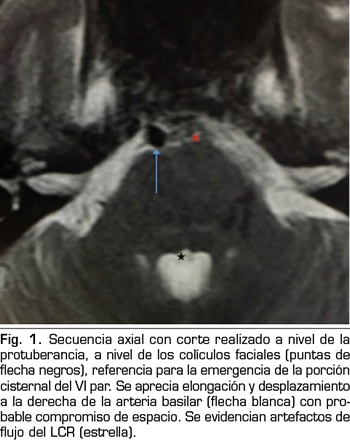

Se hace RM a los 10 días de la aparición de la diplopía objetivando un discreto agrandamiento, elongación y desplazamiento lateral derecho de la arteria basilar, con probable compromiso de espacio en la emergencia de la porción cisternal del VI par derecho (Figuras 1 y 2).

La parálisis del VI PC asociada a CPPD es un diagnóstico por exclusión que requiere la consideración de otras anormalidades neurológicas y oftalmológicas (3). Si la parálisis del VI PC ocurre dentro de las 3 primeras semanas tras la PDA y es precedida de una CPPD, es probablemente consecuencia de la PDA (4). La imagen de la RM puede revelar signos de hipotensión intracraneal, incluyendo engrosamiento meníngeo, colecciones de líquido subdurales y desplazamiento cerebral caudal (11). Estos hallazgos son debidos a la hipotensión intracraneal, sin embargo, no son específicos de la parálisis del VI PC (11). En nuestro caso, la RM no aportaba ninguno de estos signos, pero lo que sí reveló fueron datos de probable compromiso de espacio de una estructura neurológica (emergencia del VI PC derecho) por una estructura vascular (arteria basilar en nuestro caso), planteando el diagnóstico diferencial con un síndrome de compresión neurovascular. El síndrome de compresión neurovascular es definido como el contacto directo con irritación mecánica de los PC por vasos sanguíneos (7). Varios autores han comunicado casos de parálisis unilateral del VI PC, asociada con el contacto neurovascular entre el VI PC y la arteria vertebral o basilar en la RM (6).